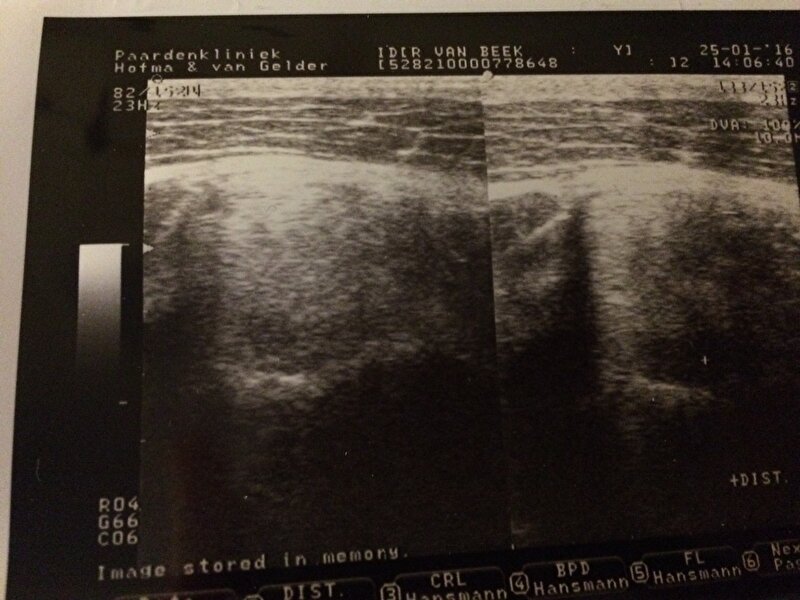

Afbeelding

Als ik me niet vergis zie je hier het verschil tussen de binnen bicepsspier en de buiten bicepsspier. Je ziet dus duidelijk een soort scheur.

Ah kijk dat maakt het al iets logischer. Ziet er heftig uit op de echo zeg, flink diep gat. Zit het gat ook op de plek van je borsttuig of juist meer op de rand (dus is het de druk van het tuig of juist de overgang van druk tot geen druk)?